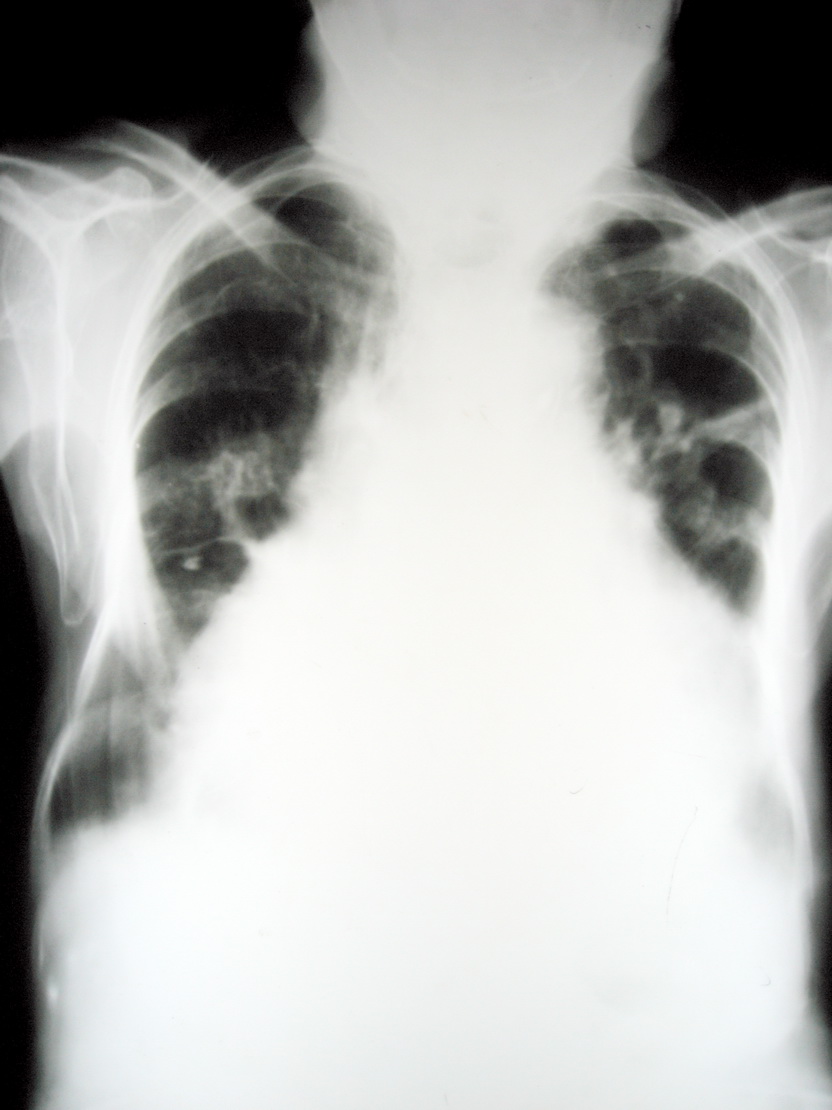

女,85岁。下肢水肿。

全心衰可能

心衰,肺水肿,心包积液。

心衰.肺水肿,胸腔少量液积

心衰 , 肺水肿 , 双侧少量胸腔积液,心包积液待除外。

全心衰,肺水肿

全心衰,心包积液,肺心病。